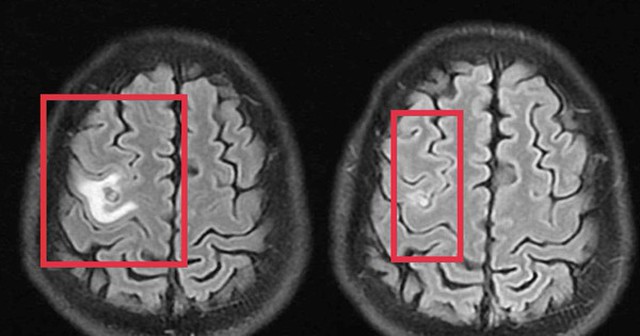

Sau khi các bác sĩ thăm khám và chụp cộng hưởng từ sọ não phát hiện một nang nhỏ ở thùy trán trái, kích thước khoảng 11 x 7 mm, kèm phù não nhẹ. Hình ảnh gợi ý tổn thương do ký sinh trùng hơn là u não nguyên phát. Xét nghiệm huyết thanh học kháng thể kháng sán dây chó dương tính, xác định chẩn đoán tổn thương não do ký sinh trùng.

Bệnh nhân được điều trị theo phác đồ, kiểm soát triệu chứng và theo dõi sát diễn biến thần kinh. Sau 10 ngày, tình trạng cải thiện rõ rệt, bệnh nhân hết tê tay, không co giật, đau đầu hay chóng mặt biến mất, toàn trạng ổn định. Bệnh nhân xuất viện và tiếp tục điều trị ngoại trú đủ liệu trình 4 tuần.

Khi tái khám gần một tháng sau, chụp cộng hưởng từ cho thấy nang não thu nhỏ rõ, phù não giảm, không còn dấu hiệu tiến triển, đáp ứng điều trị tốt.